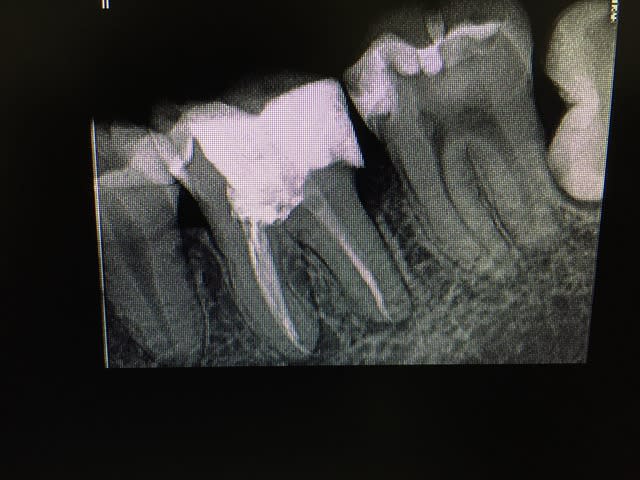

Evidemment que s'il y a pulpite il faut faire la bio... Mais s'il n'y en a pas pourquoi ne pas laisser une chance de plus à une dent?

Je n'ai jamais dit que coiffage/ collage c'est automatique ni en tout point supérieur... tout comme l'inlay core couronne ne l'est pas.

Je dis juste que l'indication médicale devrait primer et pas celui du remboursement.

Je ne veux pas dévitaliser une dent parce que j'ai besoin de faire accepter un devis inlay core couronne pour faire ma marge.

je veux dévitaliser une dent parce que j'y suis médicalement ou techniquement obligé.

Après je suis pas aussi bon que toi en endo mais il m'arrive de ne pas faire que de la merde :D (d'ailleur on peut voir que le collage ça merde aussi :D)